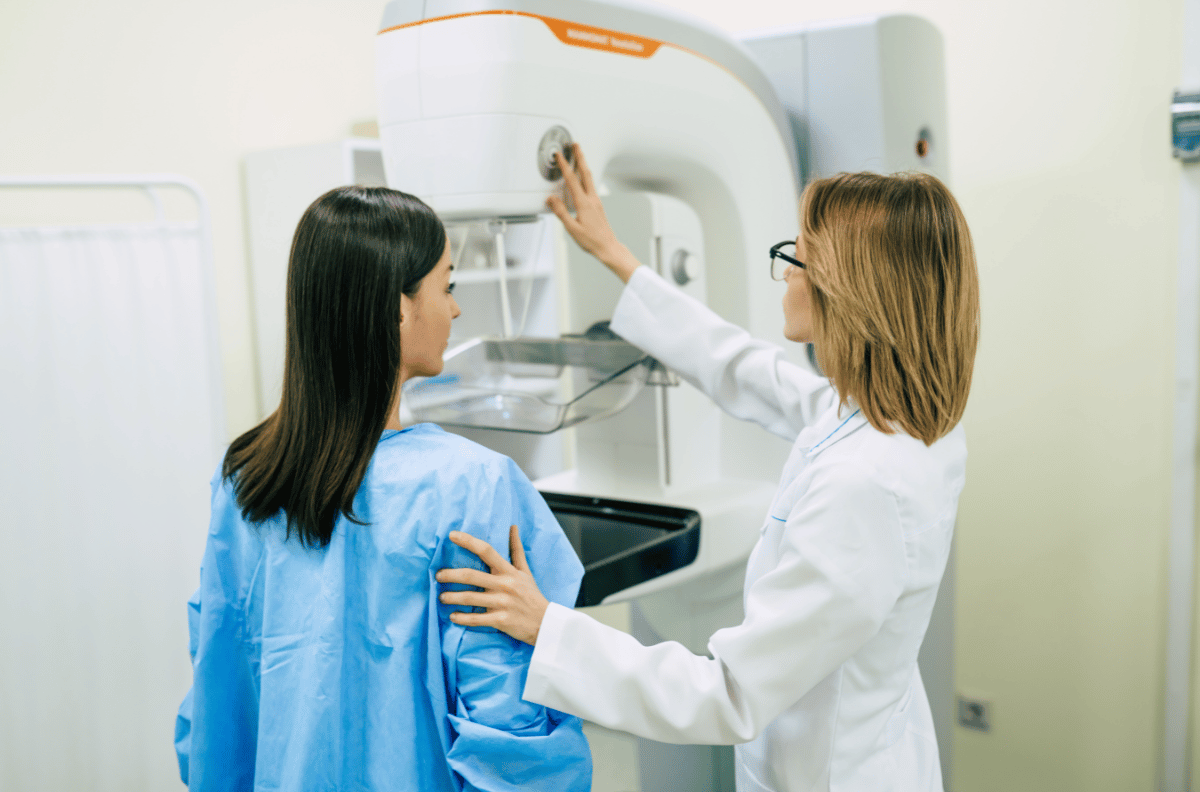

Além disso, realizamos exames laboratoriais e de imagem, incluindo exames de sangue, Doppler, eletrocardiograma, densitometria óssea, mamografia, ecocardiograma, biópsia e ultrassonografias (convencional, 3D e morfológica).

Exame das mamas para identificar possíveis sinais de câncer ou outras anomalias.

A mamografia é um exame de imagem que permite detectar precocemente o câncer de mama.